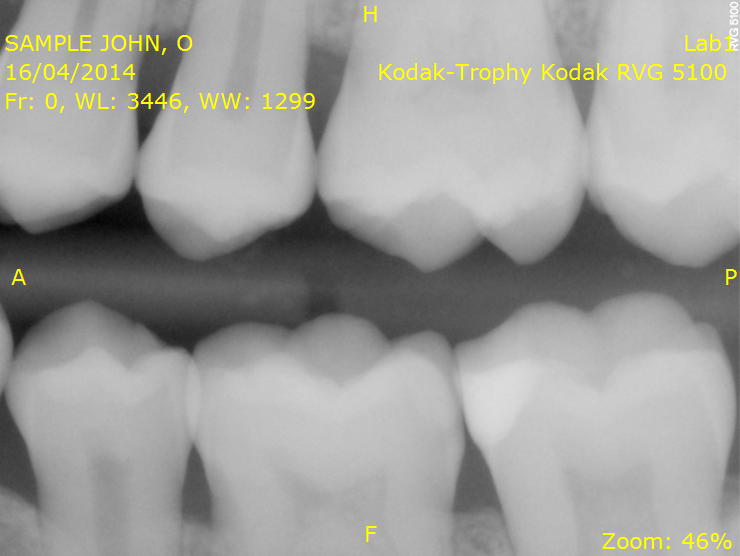

Due mesi fa ho fatto una visita di controllo da un dentista,il quale dopo avermi fatto una lastra mi diagnostica tre carie.Un mese dopo chiedo un consulto di verifica ad un altro dentista, che invece,radiografia alla mano sostiene che non esista nessuna carie.Potreste aiutarmi a capire se ho o no le carie? Io sono in possesso della radiografia,potreste visionarla e darmi un vostro parere ? Grazie e buona giornata.

radiografia (1).png